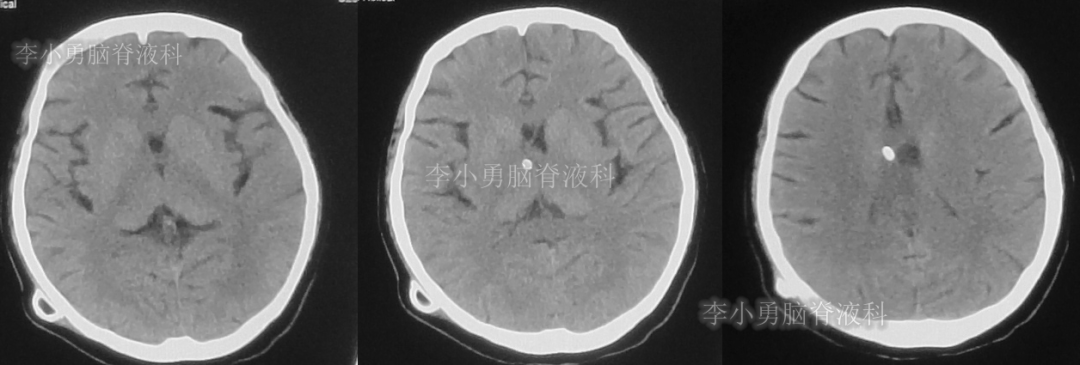

患者于2018年1月29日,突发头痛、头晕、恶心、呕吐,并高热40度。在当地医院门诊输入4天抗生素后发热缓解,但出现了双眼不能上视(眼球不能向上看)。5天后即2018年2月3日,在当地的第1家医院:浙江省海宁市某医院行头颅CT(图-1)发现脑室扩张,当地医院诊断为“梗阻性脑积水”。

图-1:2018年2月3日头颅CT